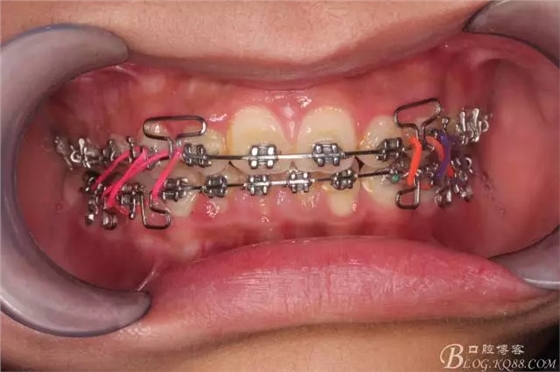

佩戴三個月的FR2, 效果奇佳!前牙基本達到淺覆蓋,淺覆合!接下來進入二期直絲弓固定正畸,排齊階段!

下頜配合多曲方絲,三角牽引,調整咬合。

中線不齊,咋辦?繼續(xù)哄哄患者配合,2牽+斜牽。